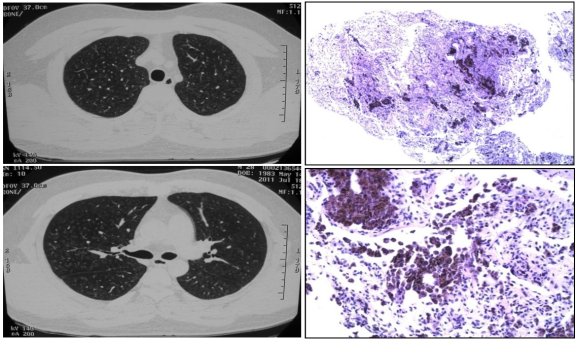

病例:男,48岁,接触钴酸锂5.5年。治疗前胸部HRCT,显示双肺磨玻璃影,以及马赛克影:

ero为什么不显示叶俏教授:HRCT是发现和鉴别「过敏性肺炎」的重要环节,何种表现指向预后不良?使患者发病的危害因素躲在哪些环境中?_https://www.jmylbn.com_新闻资讯_第47张

脱离暴露和糖皮质激素3月后,胸部HRCT较前改善:

ero为什么不显示叶俏教授:HRCT是发现和鉴别「过敏性肺炎」的重要环节,何种表现指向预后不良?使患者发病的危害因素躲在哪些环境中?_https://www.jmylbn.com_新闻资讯_第48张

外科肺活检,肺组织病理提示巨细胞性间质性肺炎(GIP)。

ero为什么不显示叶俏教授:HRCT是发现和鉴别「过敏性肺炎」的重要环节,何种表现指向预后不良?使患者发病的危害因素躲在哪些环境中?_https://www.jmylbn.com_新闻资讯_第49张

ero为什么不显示叶俏教授:HRCT是发现和鉴别「过敏性肺炎」的重要环节,何种表现指向预后不良?使患者发病的危害因素躲在哪些环境中?_https://www.jmylbn.com_新闻资讯_第50张